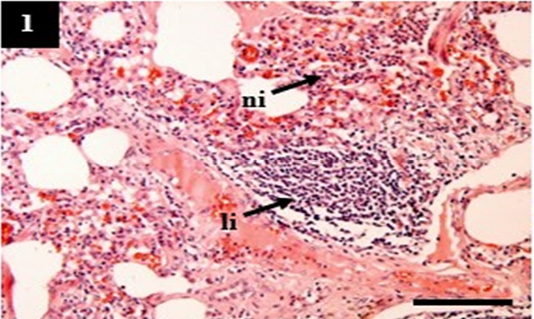

Histopathology of lung from case C1 showed predominantly infiltration of neutrophil (ni) and lymphocytes (li) within the pulmonary interstitial. H&E, 10×.